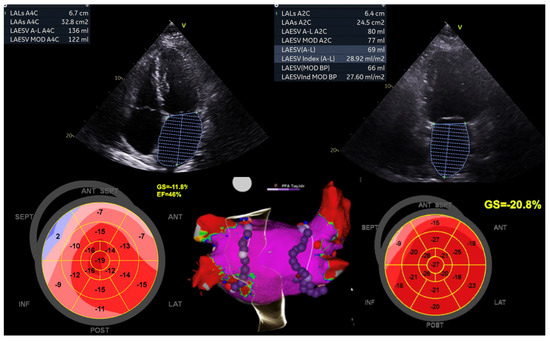

Figure 5. This image emphasises the positive impact of atrial fibrillation (AF) ablation on enhancing outcomes and quality of life for a 64-year-old woman with persistent AF and HFmrEF. Initially, she had a baseline left ventricular ejection fraction (LVEF) of 46%, a left atrial area (LAA) of 32.8 cm2, and a 100% AF burden. Following AF ablation (pulmonary vein isolation), her LVEF percentage significantly increased to 68%, and her LAA reduced to 24.5 cm2 within 3 months, accompanied by an improvement in global longitudinal strain (GLS) from −11.8% to −20.8%. Subsequent Holter monitoring showed no AF recurrence. Image courtesy of the Canberra Heart Rhythm Centre.